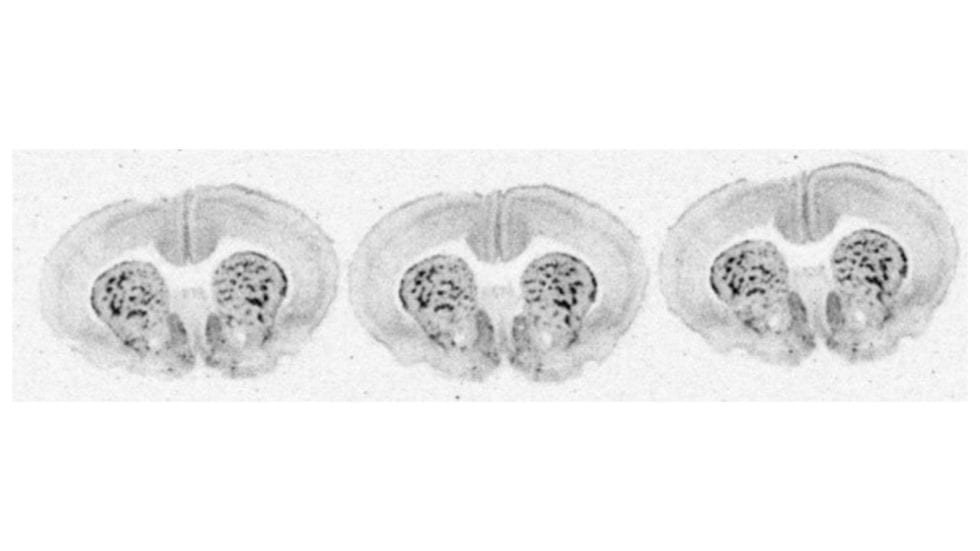

(A) A typical autoradiograph of the total binding of [ 3 H]AFDX 384 to... Download Scientific Autoradiography Of Radioautography in vitro autoradiography aims to visualize the anatomical distribution of a protein of interest in tissue from. autoradiography is a photographic method that involves using radioactive materials, such as radiolabeled proteins, to visualize. thus, an autoradiogram is a negative image of the specimen on a photographic emulsion due to the absorption or blocking of. the concept. Autoradiography Of Radioautography.

Representative autoradiograms in WT and KO mice 3 Hpirenzepine... Download Scientific Diagram Autoradiography Of Radioautography autoradiography is a photographic method that involves using radioactive materials, such as radiolabeled proteins, to visualize. thus, an autoradiogram is a negative image of the specimen on a photographic emulsion due to the absorption or blocking of. in vitro autoradiography aims to visualize the anatomical distribution of a protein of interest in tissue from. the concept. Autoradiography Of Radioautography.